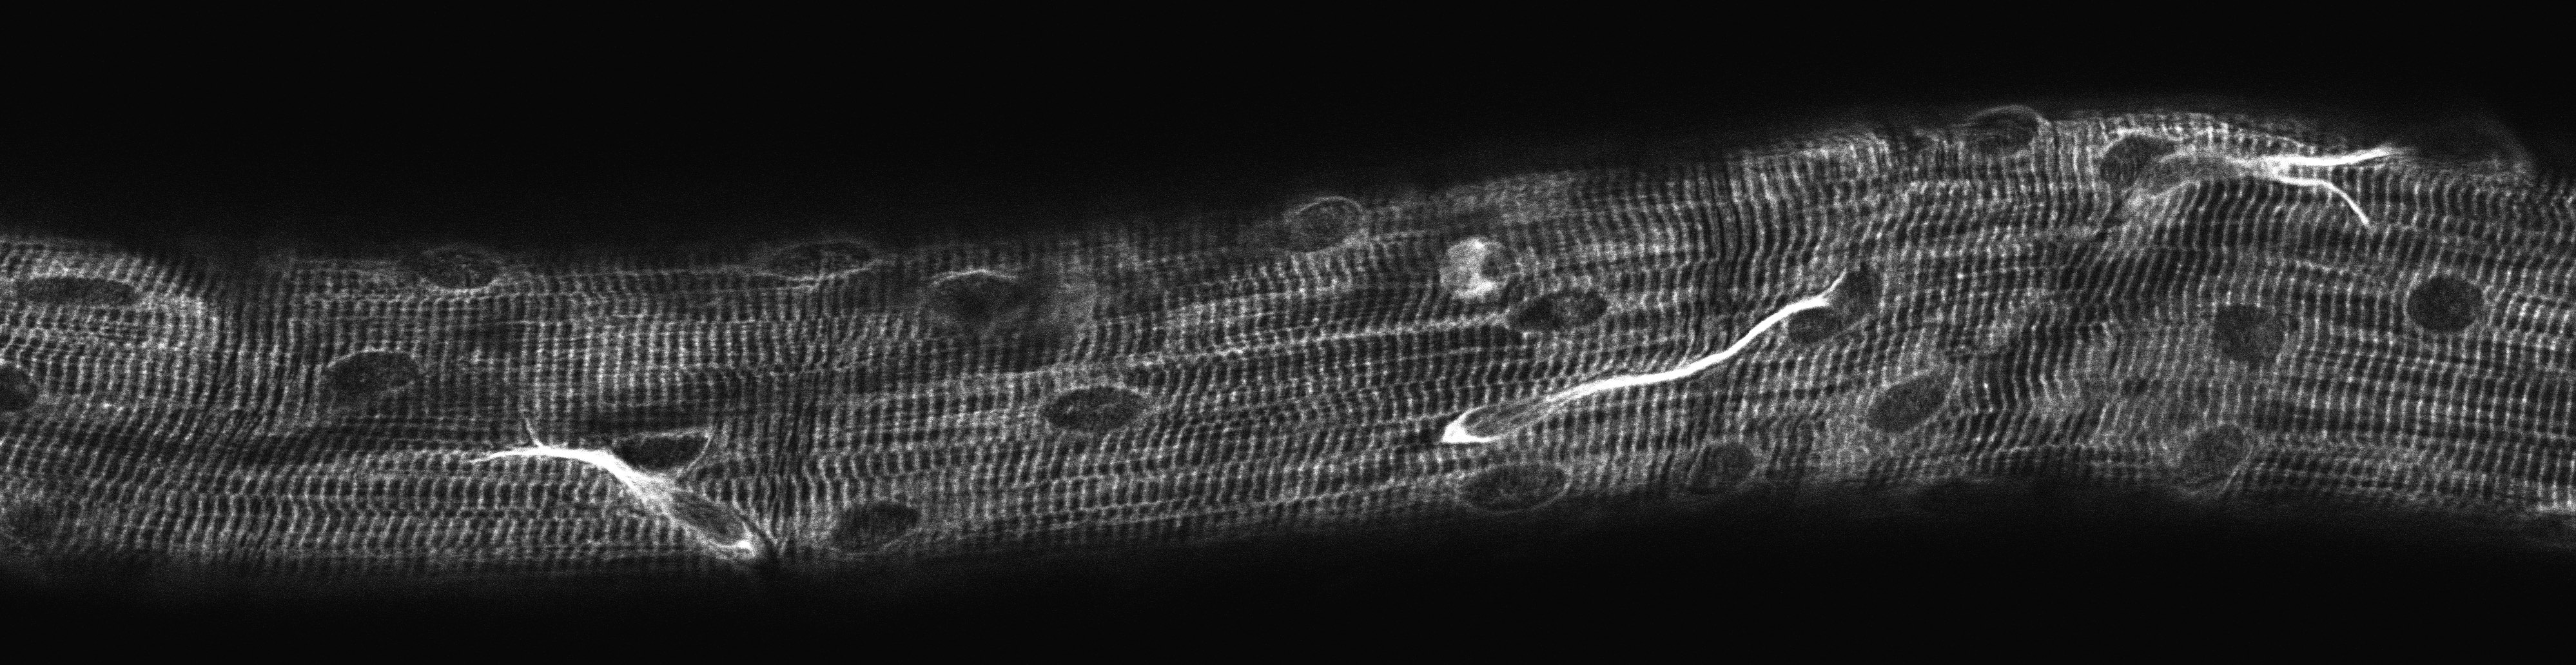

Disputatforsvar — This thesis is focused on satellite cells (the stem cells of skeletal muscle) in humans with ageing, and in response to exercise loading, spanning from experimentally induced myofibre necrosis at one end of the spectrum, to lifelong endurance exercise at the other.

”Satellite cell activity in human skeletal muscle with exercise and during regeneration”